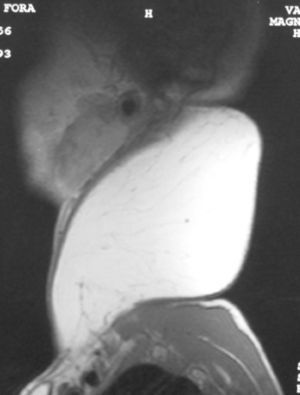

Se decide realizar resonancia magnética (RM) cérvico-facial en la que se evidencia una masa homogénea, bien delimitada que no invadía estructuras vecinas y con una densidad grasa (figs. 2-4).

Las técnicas de imagen como la RM nos ayudan a determinar la exacta localización y las relaciones de la masa con las estructuras anatómicas de la vecindad. Estos tumores aparecen como masas homogéneas y radiolúcidas tanto en la RM como en las radiografías. En las RM son isointensas en relación con la grasa subcutánea8,9.